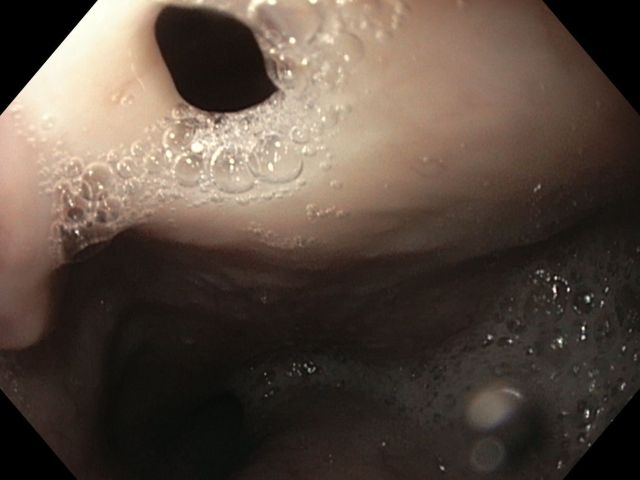

A mantle of rosaries along the colon

2º Prémio - Fotografia